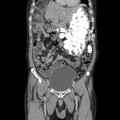

Moški tarnal zaradi bolečin v želodcu, zdravnike pa je skoraj kap

Poglejte, kaj so odkrili v njegovem želodcu.